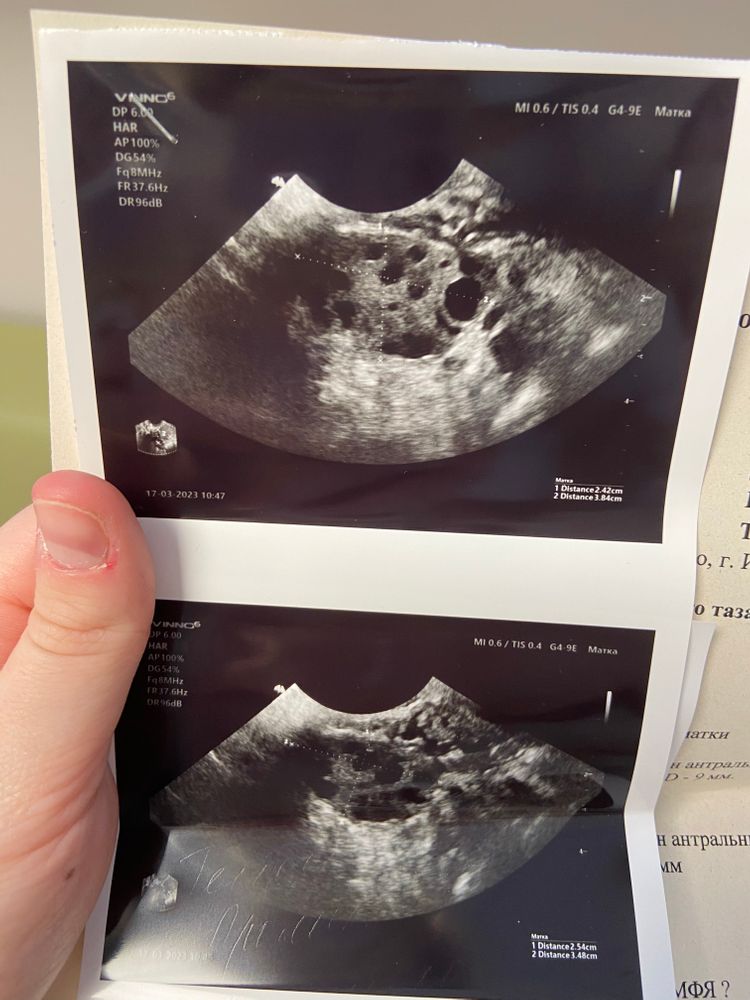

Девочки, была сегодня на узи первой фазы цикла. Вот такая картина, у кого было подобное ? Через сколько забеременели?

Яичник правый

35х22

Яичник правый комм

распологается у ребра матки

эхоструктура однородная

фолликулярный аппарат представлен антральными фолликулами : множественными ( 10 в срезе ) мах D - 9 мм.

Яичник левый

26х22

Яичник лев комм

распологается типично

фолликулярный аппарат представлен антральными фолликулами в достаточном количестве мах D - 5 мм

Заключение

Заключение УЗ - признаки 1 фазы менструального цикла . МФЯ ?

Рекомендовано: консультация гинеколога / контроль узи омт